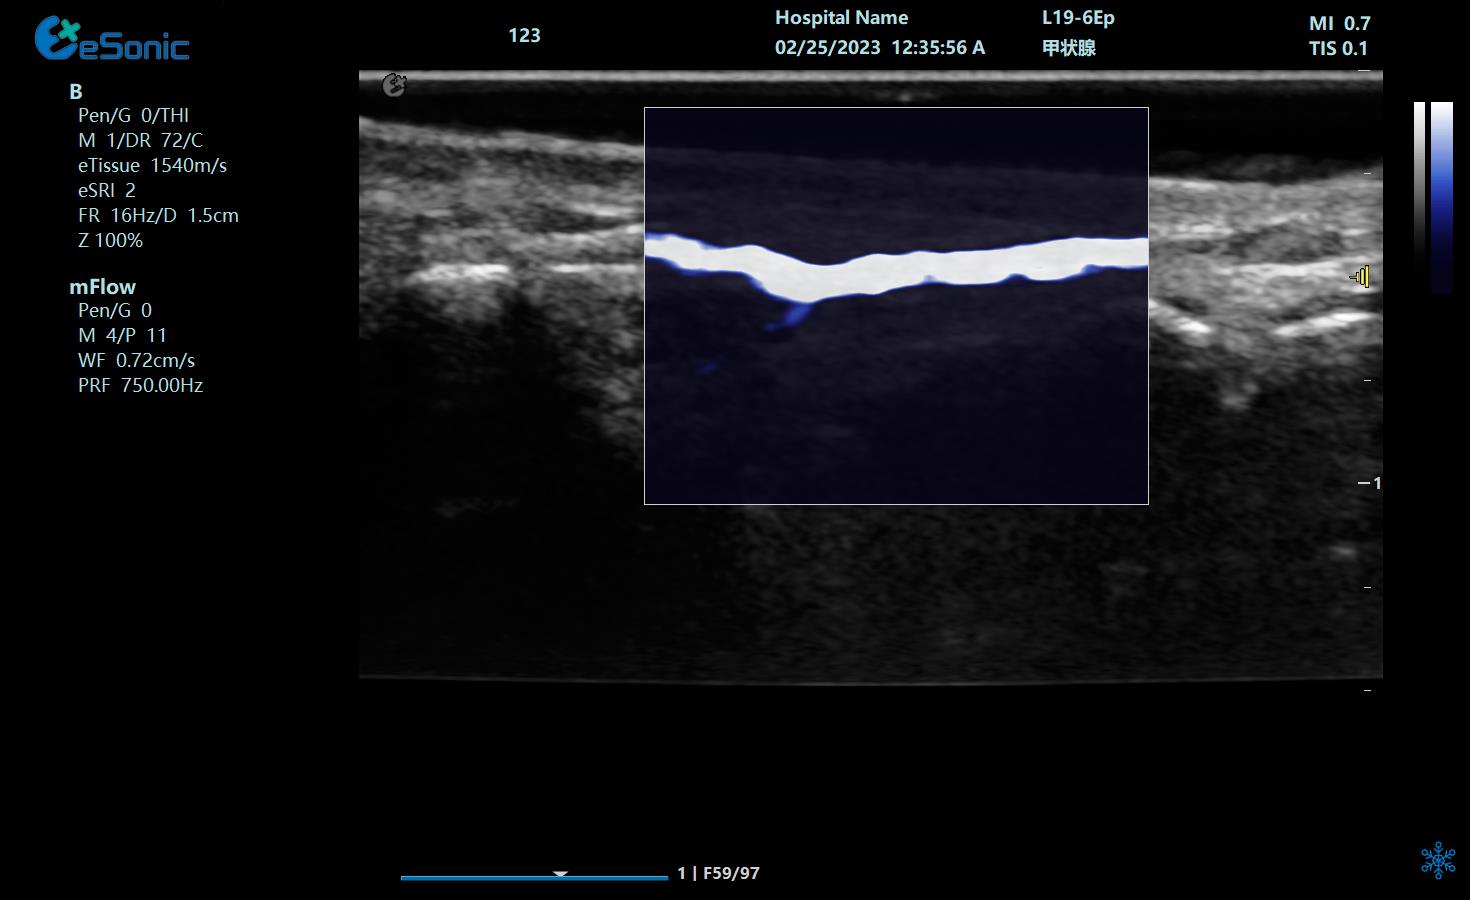

重症肺部超声

超声声像图:声束垂直胸膜线时,可见多条A线与胸膜线平行,且等间距。

image.png

探头:高频线阵探头

部位:放置于腋前线与腋中线,7/8肋间或8/9肋间,沿肋间隙放置,观察和测量膈肌的厚度。

功能:M型超声,膈肌测量包